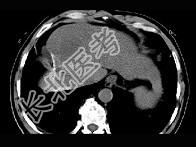

- 单项选择题女性,56岁, 腹胀、双下肢水肿、乏力、食欲不振,影像所见如下图, 最佳的诊断是  (    )

- A、酒精性肝硬化并肝血管瘤

- B、血吸虫肝硬化并肝癌

- C、肝炎后肝硬化并肝癌

- D、局限性脂肪肝

- E、原发性肝癌